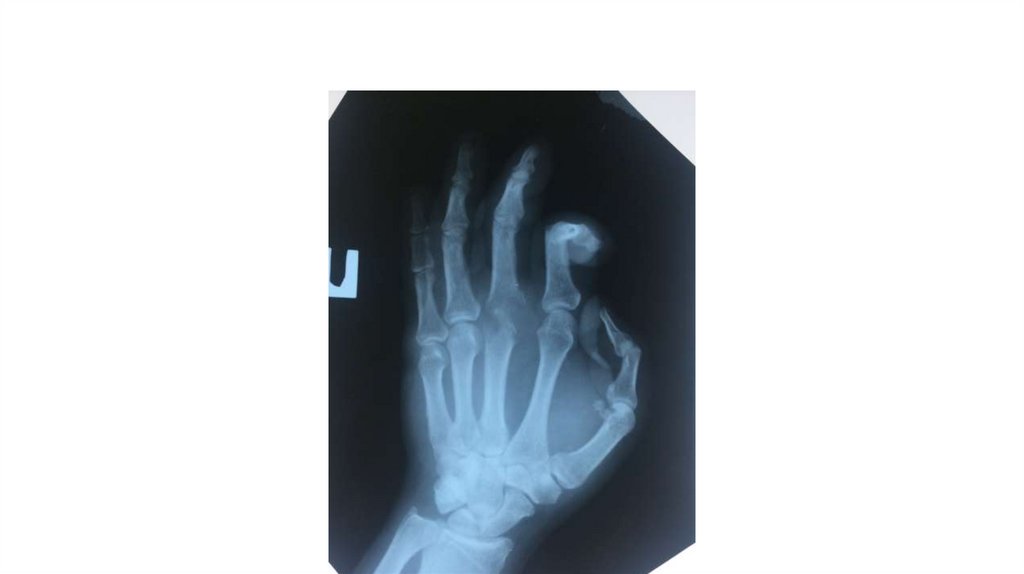

Воспалительные заболевания опорнодвигательного аппарата

«Воспалительные

заболевания опорнодвигательного аппарата»